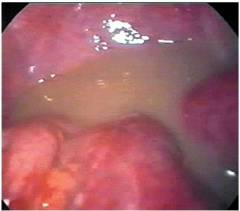

Фото эндоскопической диагностической операции при пельвиоперитоните в результате осложнения кисты яичника. В брюшной полости гной, на брюшине признаки воспаления.